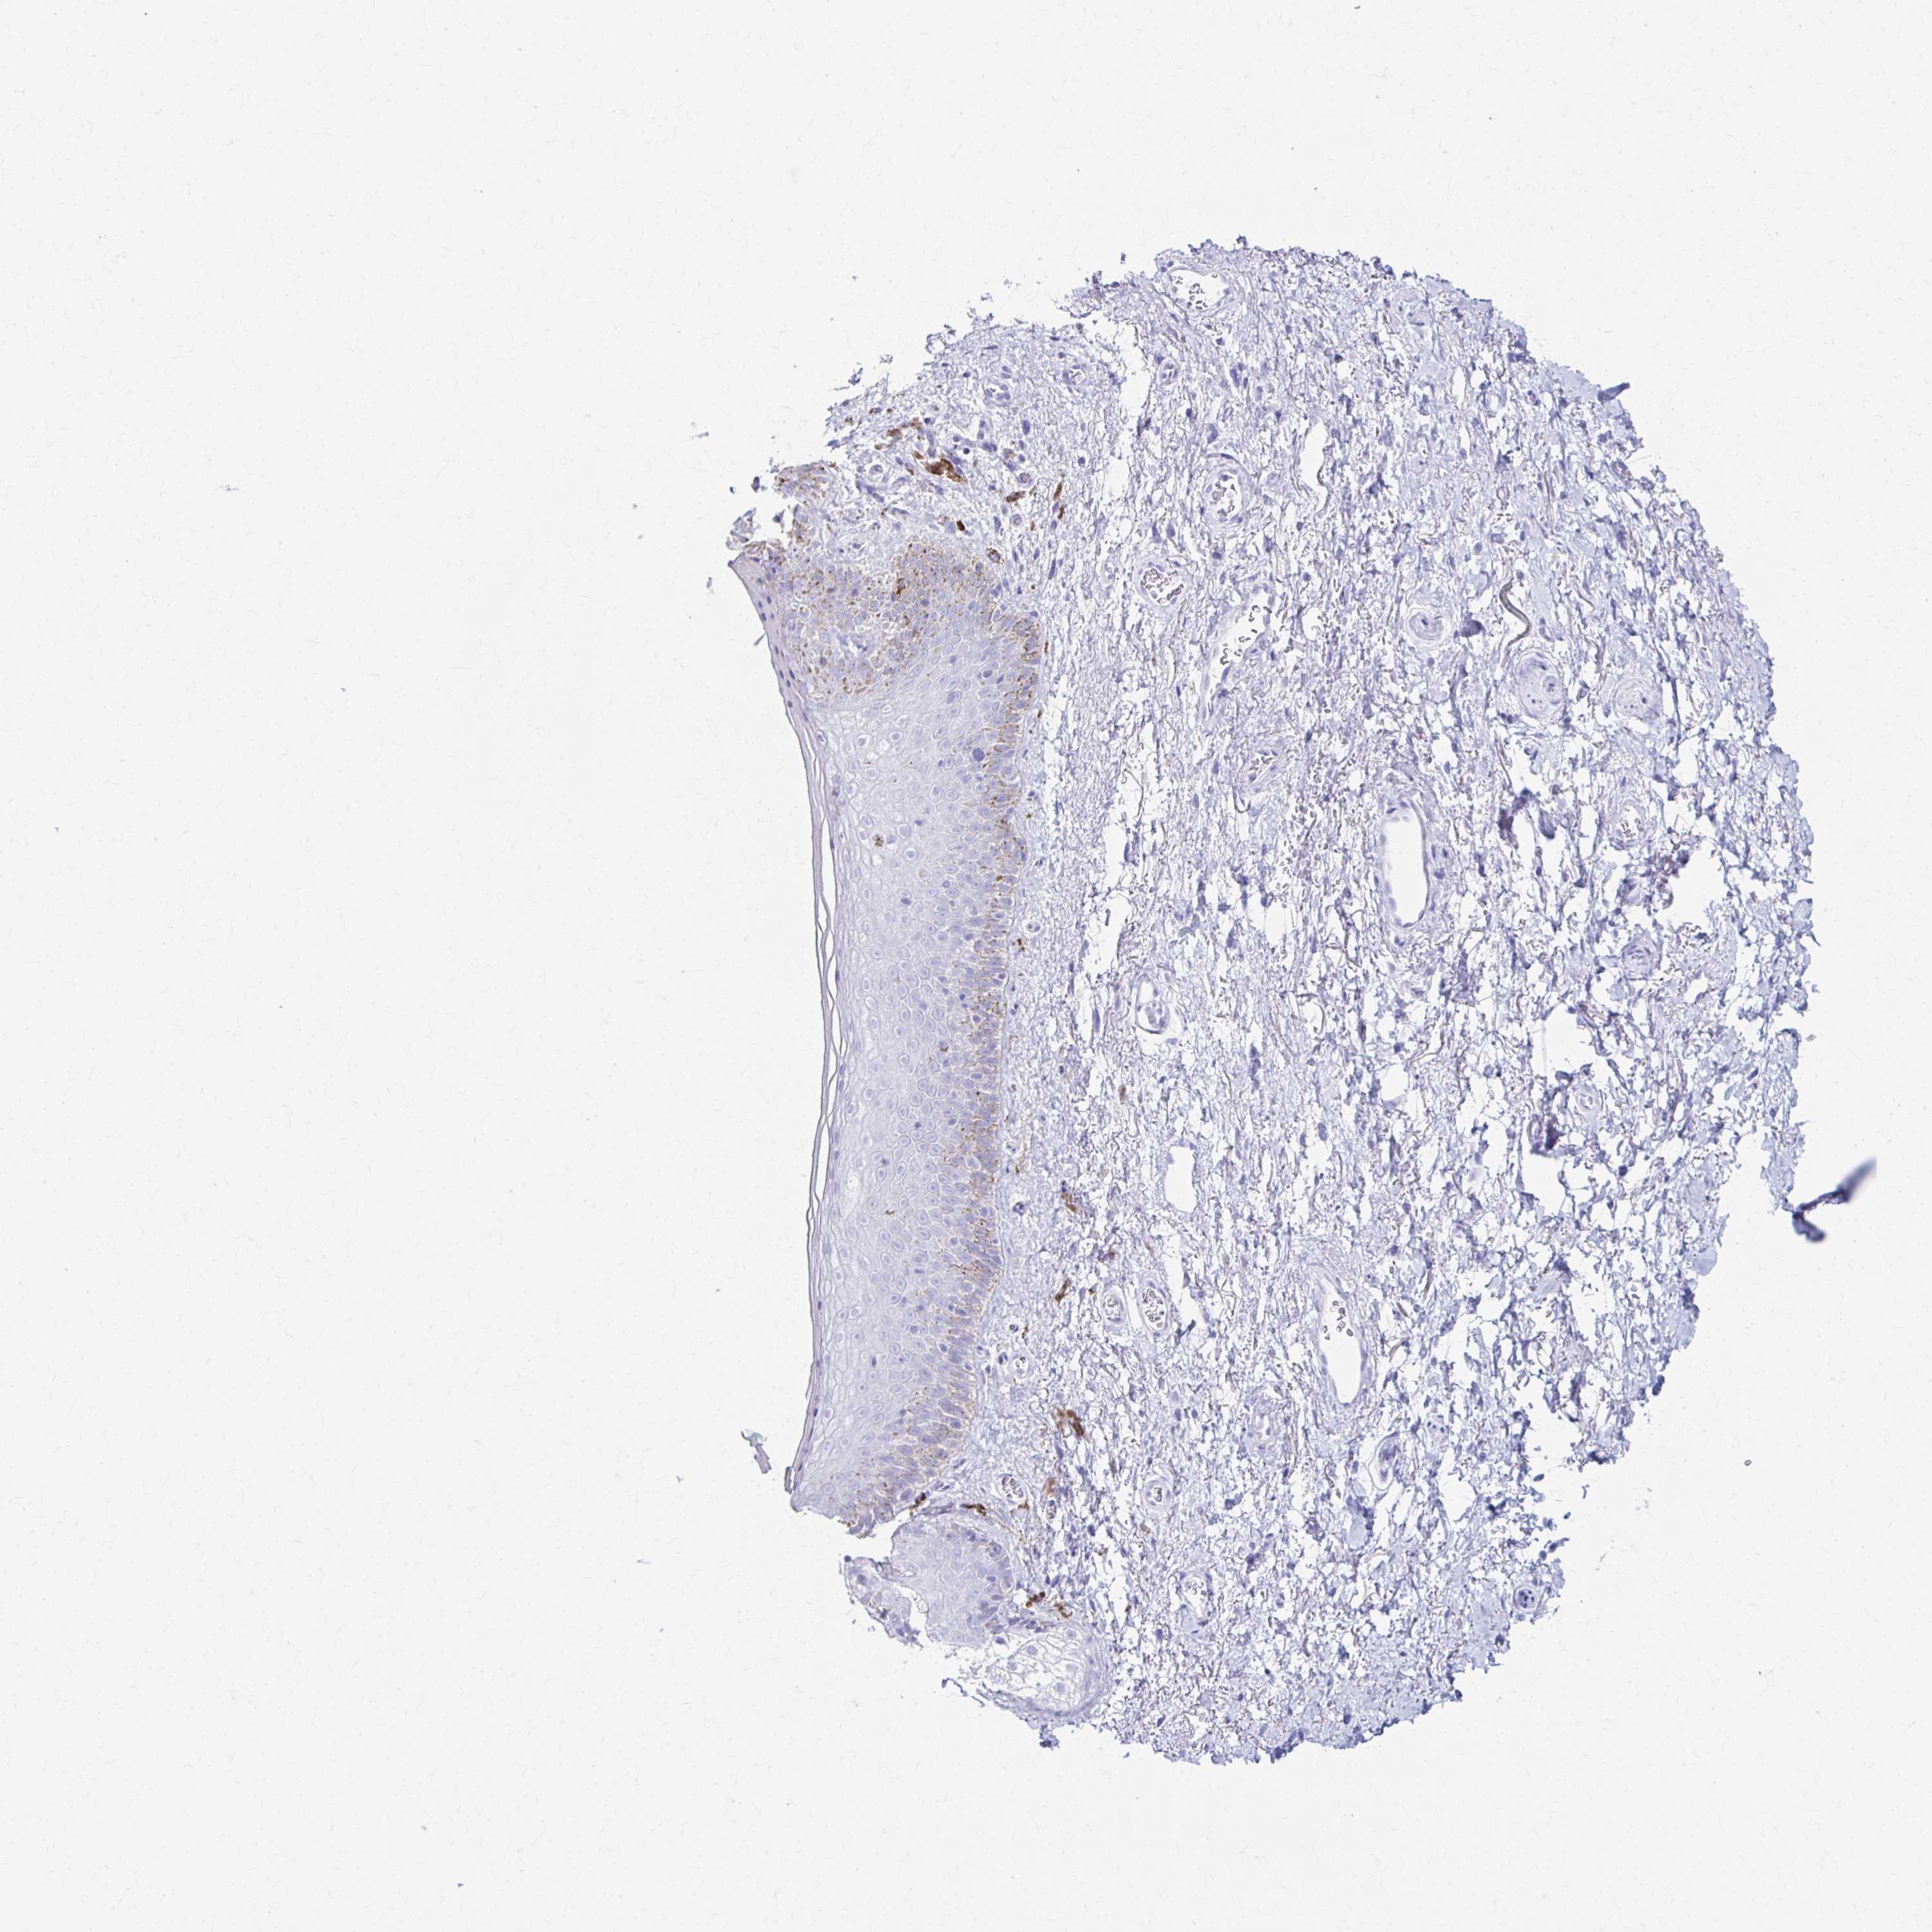

PRKCG